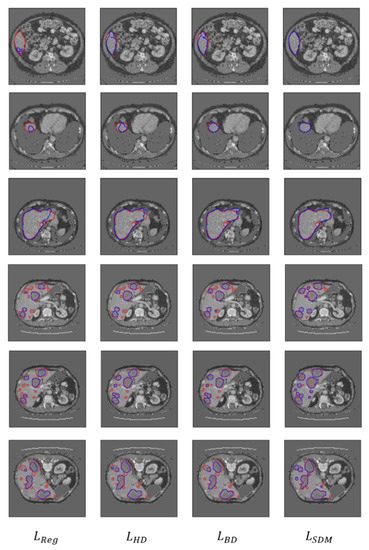

3.2.2. Qualitative Evaluation